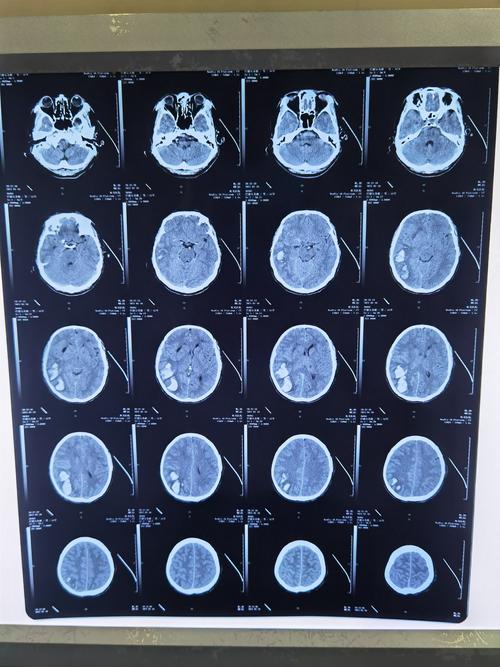

脑出血片子图片解析

脑出血片子图片解析,脑出血检查报告单图片

脑出血ct影像表现图片

脑出血ct图片解说图

脑出血片子

脑出血图片ct

脑出血ct